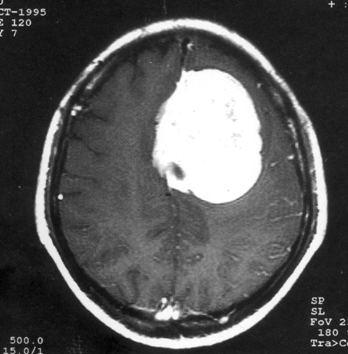

问题 病历摘要:??患者女性,37岁。大便时突起炸裂样头痛3小时,伴喷射样呕吐。既往体健。体检:T37.5℃,BP145/90mmHg,R20次/分,P85次/分。神志清楚,颅神经检查无异常,颈强直,克、布氏征(-),四肢肌力、肌张力正常,病理征(-)。 根据病史,最可能的诊断是什么?

选项 A.脑栓塞 B.脑血栓形成 C.蛛网膜下腔出血 D.脑炎 E.血管性头痛 F.脑膜炎 G.脑出血

答案 C